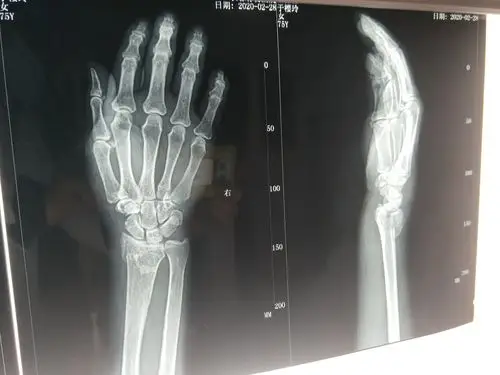

右桡骨远端骨折,手法整复

桡骨远端骨折手法复位前后对比 - 好大夫在线